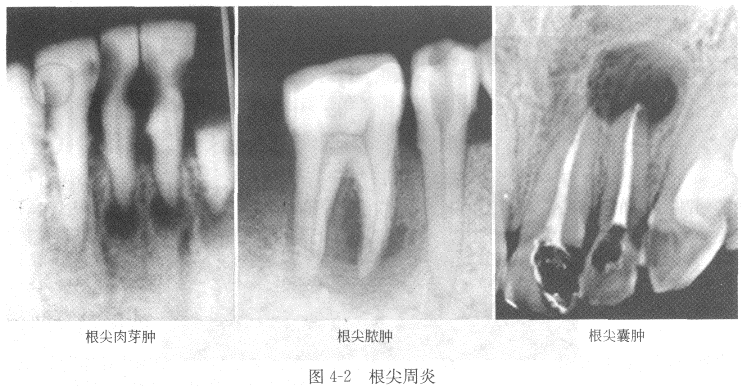

依病变的性质不同,分为三种(图4-2)。

(1)慢性根尖脓肿 X线表现为患牙根尖区有一边界清楚但不十分整齐锐利的低密度透射区,形状规则或不规则,密度不均匀,根尖区骨硬板消失。

(2)根尖肉芽肿 X线表现为位于患牙根尖区形态规则,呈圆形或椭圆形的骨质破坏区,直径多不超过1cm,周界清晰,但无致密的骨白线。

(3)根尖囊肿 X线表现为位于患牙根尖的形状规则、边缘清晰锐利的低密度透射区,呈圆或椭圆形。病源牙的根尖位于囊腔中,牙周膜间隙及硬骨板消失,囊肿边缘有一薄层致密的骨白线。